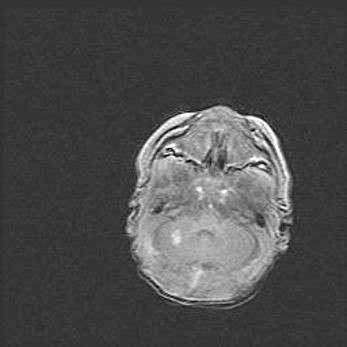

Множественные кисты обоих полушарий головного мозга, наибольшая из них в правой затылочной области. Ассиметричная атрофическая гидроцефалия.

Возраст: 7 месяцев

Вес: 5660 г

Пол: мужской

Окружность головы: 41,5 см

Срок гестации: 28-29 недель

Кисты головного мозга развиваются в результате многоочаговых некрозов вещества мозга и возникают вследствие перенесенной перинатальной инфекции, менингитов, энцефалитов, асфиксии, родовой травмы, расстройств мозгового кровообращения различного генеза. Образованию кист в веществе головного мозга плодов и новорожденных способствуют такие факторы, как высокое содержание в нем воды, недостаточная (или отсутствие) миелинизация и слабая астроглиальная реакция на повреждение.

Кисты могут сочетаться с гидроцефалией и другими поражениями головного мозга.